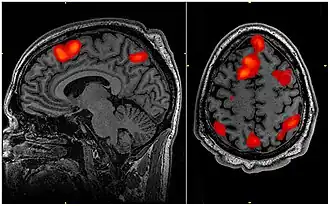

Funkcjonalne obrazowanie metodą rezonansu magnetycznego, zwyczajowo funkcjonalny rezonans magnetyczny, w skrócie fMRI (od ang. functional magnetic resonance imaging) – wyspecjalizowana odmiana obrazowania metodą rezonansu magnetycznego, za pomocą której mierzony jest wzrost przepływu krwi i utlenowania aktywnej okolicy mózgu. W metodzie tej wykorzystywany jest fakt, iż podczas aktywności komórek nerwowych zwiększa się ich zapotrzebowanie na tlen i nasila się produkcja dwutlenku węgla. Wzrost aktywności danego rejonu mierzy się przy pomocy odpowiedzi BOLD (ang. blood-oxygenation-level-dependent), która określa zależność intensywności sygnału rezonansu magnetycznego od poziomu natlenienia krwi[1].

Przed badaniem pacjent proszony jest o zdjęcie metalowych elementów ubrania i biżuterii. Następnie pacjent kładzie się na łóżko, a jego głowę umieszcza się w tubie. Indukcja magnetyczna wytwarzana w skanerach może wynosić od 1 do 7 T. W celu stłumienia głośnych i nieprzyjemnych dźwięków wewnątrz skanera powodowanych m.in. przez prąd płynący przez cewkę elektromagnesu, pacjent zakłada słuchawki ochronne lub zatyczki. W czasie badania, w zależności od jego celu, pacjent najczęściej proszony jest o rozwiązanie zadań. Zadania mogą polegać na powtarzaniu słyszanych słów, liczeniu, dopasowaniu odpowiedniego podpisu do widocznego na ekranie obrazka za pomocą naciśnięcia odpowiedniego przycisku, stworzeniu odpowiedniego słowa, czy poruszeniu odpowiedniej kończyny. W wyniku badania pacjent otrzymuje mapę mózgu z widocznymi rejonami aktywności.